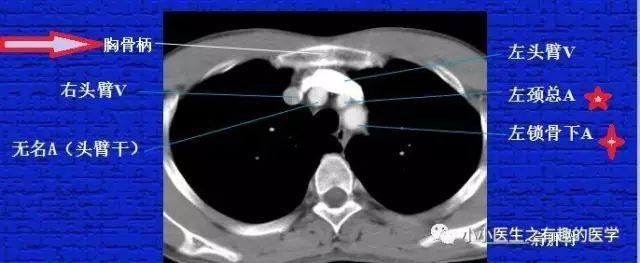

2.要知道胸锁关节,进一步提高解剖知识要用到。

3.要知道胸骨柄,进一步提高解剖知识要用到。要知道肩胛骨,因为肩胛骨下端一般是第七肋间,胸腔穿刺要用。

最下边的是锁骨下动脉,锁骨下动脉上边的是颈总动脉。